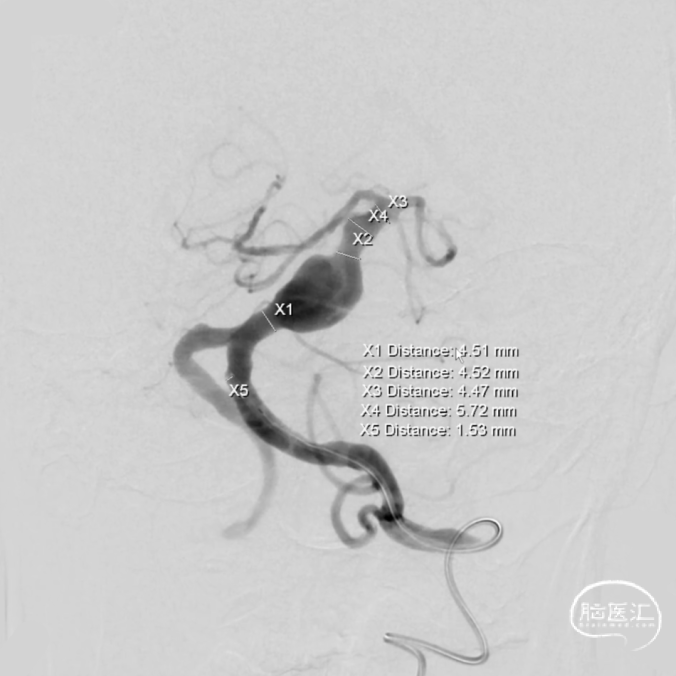

术前测量:

覆盖长度:49mm

直径:

远端锚定点:4.47mm

瘤颈远端:4.52mm

瘤颈近端:4.51mm

选择Lattice血流导向密网支架

5.3mm*41mm,9个球囊